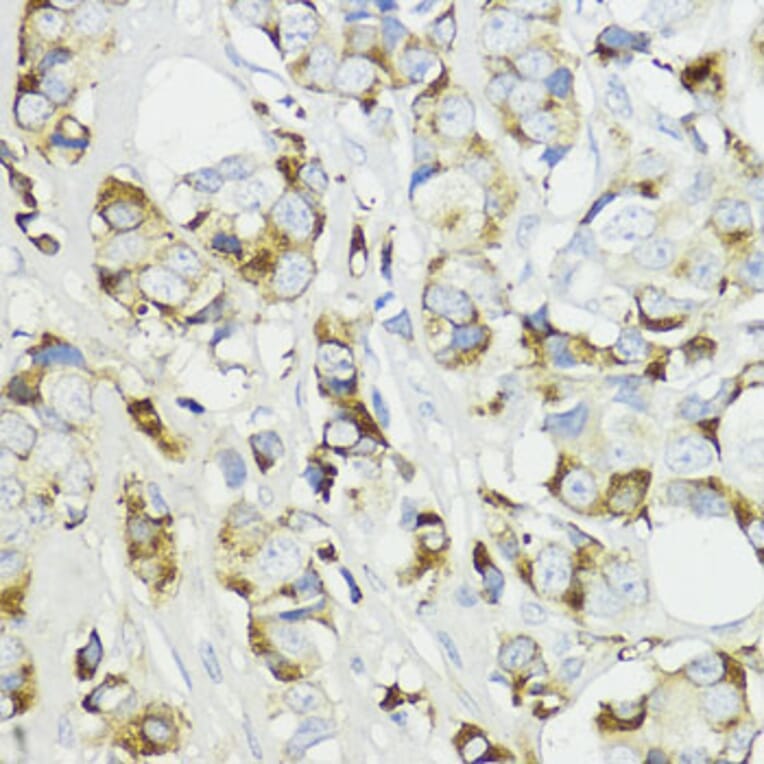

Immunohistochemistry - Anti-Complement factor B Antibody (A13606)

Immunohistochemistry analysis of paraffin-embedded human mammary cancer using Anti-Complement factor B Antibody (A13606) at a dilution of 1:200 (40x lens). Perform microwave antigen retrieval with 10 mM PBS buffer pH 7.2 before commencing with IHC staining protocol.